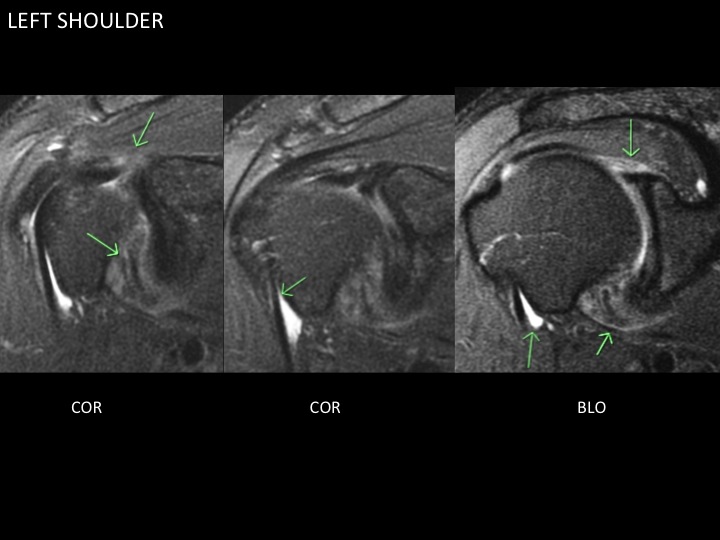

45 yr old male with 6 months bilateral shoulder pain and LROM

Figure 1 for case adhesive capsultis

Figure 1

Despite the female predilection for adhesive capsulitis, here is a case of bilateral adhesive capsulitis in a male, more severe on the left. Up to 40-50% sequential bilateral involvement has been reported, though simultaneous bilaterality is rare. In the left shoulder, bright signal at the articular surface of the cuff near the supraspinatus insertion is more likely capsular inflammation than cuff pathology (not seen on the Rt where involvement is more limited to the axillary recess). Note the disproportionate fluid distention of the biceps sheath, more apparent on the left.

adhesive capsultis